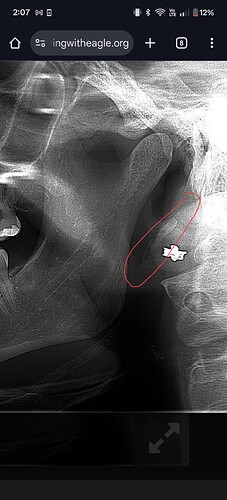

@Cin89 see attached annotated imaging.

Can visually see calcified stylohyoid ligament on both sides. On your left side your styloid is normal length, followed by a small section of normal stylohyoid ligament, but then followed by calcified stylohyoid ligament. On your right side, it appears to be one continuous chunk of calcification. Nonetheless, they pass C1, an area where the IJVs pass by, so it’s possible your IJVs are being compressed. A head and neck CT with contrast would be an important next step. It will allow the radiologist to measure the calcifications and assess for IJV compression. Unfortunately, unless there is contrast involved, a CBCT won’t show vascular compression.

thank you so much. this is helpful and gives me some ideas of what to research online lol are you able to tell me what the area I circled in blue is? It almost looks like it follows or connects to the area you circled but there is a gap in between. Is this a bone? thanks again for your insight

The blue circled area is the hyoid bone process, which does look possibly a bit longer than average, when you get a CT does, as long as it covers the skull base to the hyoid bone then it’ll be easier to tell if it’s potentially an issue…

What you’ve circled in blue is either the hyoid greater horn, or more calcified stylohyoid ligament extending off the lesser horn of the hyoid. CBCT will help figure that out. Just unfortunate that the CBCT won’t further our understanding of any vascular compression that may be occurring